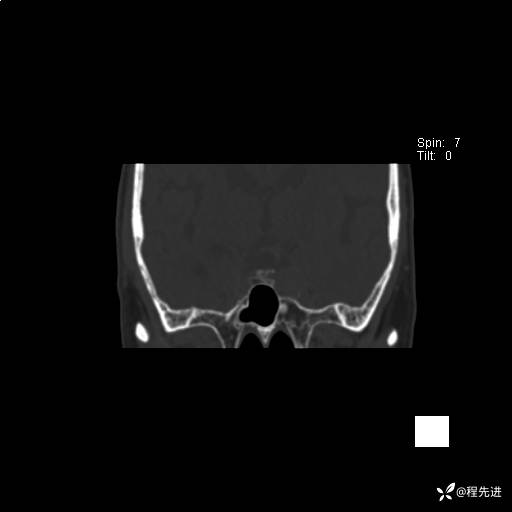

CT平扫: